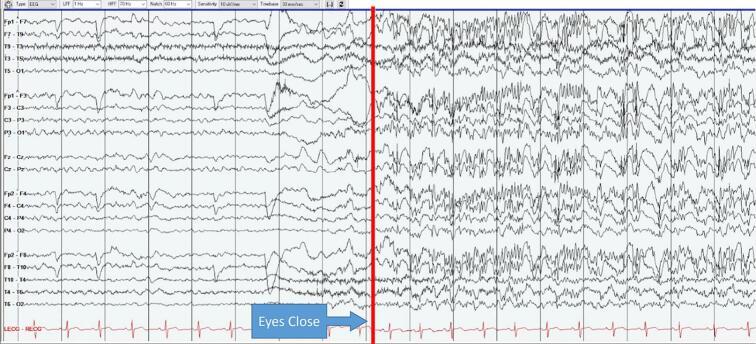

Cerebrotendinous Xanthomatosis (CTX) is a rare autosomal recessive condition resulting in accumulation of cholesterol and cholestanol due to disrupted bile synthesis. Affected tissues include brain, tendons, skin, bone, lungs, and eyes. We report a clinical case presenting with epilepsy, which has been described, however with a particular EEG appearance that appears novel with Fixation-Off Sensitivity (FOS). The patient's EEG showed significant buildup of abnormal slowing and frontally predominant generalized epileptiform discharges when her eyes were closed, and in contrast essentially normal tracings while eyes were open, eventually showing electrographic evolution and generating a bilateral tonic-clonic seizure. Genetic testing confirmed the diagnosis of CTX, and CTX-specific treatment with chonodeoxycholic acid was initiated in addition to anti-seizure medication.

脑腱性黄瘤病(CTX)是一种罕见的常染色体隐性疾病,由于胆汁合成受阻导致胆固醇和胆甾烷醇蓄积。受累组织包括脑、肌腱、皮肤、骨骼、肺和眼睛。我们报告了一例以癫痫为表现的临床病例,此前已有相关描述,但该病例具有一种特殊的脑电图表现,即闭眼时出现对闭眼敏感(FOS)的异常慢波显著增强以及以额部为主的广泛性癫痫样放电,而睁眼时脑电图基本正常,最终出现脑电图演变并引发双侧强直阵挛性发作。基因检测确诊为CTX,除抗癫痫药物治疗外,开始使用鹅去氧胆酸进行CTX特异性治疗。